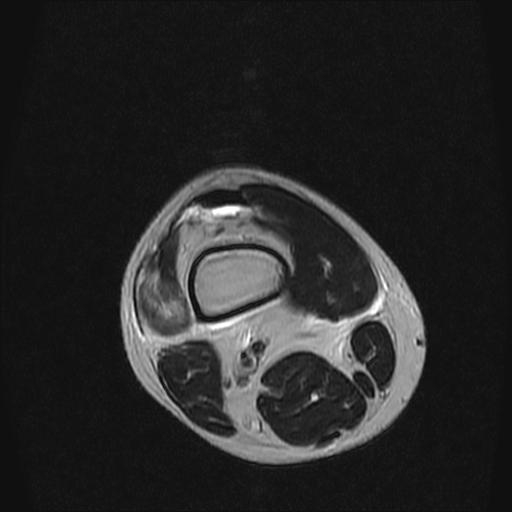

标题: MRI1265:男性40岁,右膝关节 [打印本页]

标题: MRI1265:男性40岁,右膝关节

40岁男性,右膝关节外伤,x光平片示,髁间隆突撕脱骨折。

1、前交叉韧带撕裂;

2、外侧半月板后角撕裂;

3、关节腔积液。

前交叉韧带撕裂,关节腔积液.

半月板1-2级损伤   前交叉韧带撕裂伤   关节腔少量积液  诸骨未见新鲜外伤性改变

髁间隆突撕脱骨折;内侧副韧带损伤。

1、内侧副韧带撕裂;

2、前交叉韧带撕裂;

3、滑膜炎伴关节腔积液。

内侧副韧带撕裂及关节腔积液是肯定的,但是前交叉撕裂确定吗?会不会有容积效应的因素,因为前一张前交叉显示清楚,连续性良好,且较光滑。请问楼主有关节镜支持吗?我们医院也经常有这样的患者,但苦于没有关节镜,而无法对照、证实(除非完全断裂),出现了不同的诊断结果只能毫无意义的争论。

除了关节积液外并无韧带撕裂,acl胫侧附着点有2束,正常情况下脂肪信号。此病例应加做压脂像以便观察是否有骨损伤。